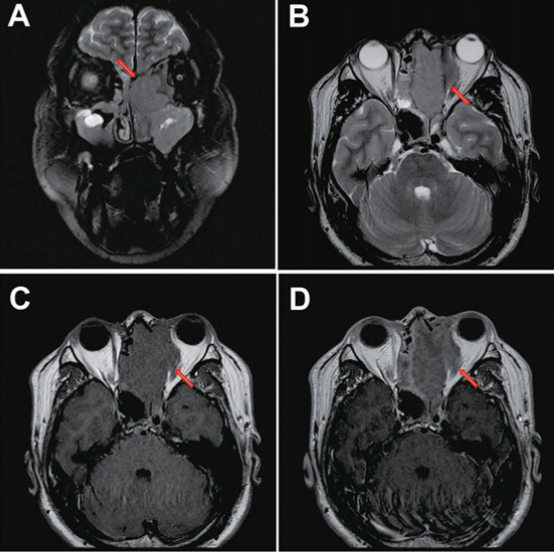

Os tumores de SNC são as neoplasias sólidas mais comuns na infância, com 50-60% localizados na fossa posterior (infratentoriais). Os sintomas variam drasticamente com a localização:

- Tumores Infratentoriais (Fossa Posterior):

- Sintoma clássico: Hidrocefalia obstrutiva. Isso se traduz em cefaleia crônica e progressiva, irritabilidade e, classicamente, vômitos matinais.

- Ataxia: Ocorre por afetação do cerebelo.

- Em lactentes: Os sintomas de HIC podem ser mascarados pelo aumento do perímetro cefálico (PC) e abaulamento de fontanela.

- Tumores Supratentoriais:

- Sinal clássico: Crises epilépticas de início abrupto.

- Podem apresentar déficits motores/sensitivos focais ou alterações comportamentais.

- Tumores de Tronco Encefálico:

- Apresentam-se com déficits de nervos cranianos (ex: estrabismo, perda auditiva) e déficits motores.

O diagnóstico é feito por TC ou RNM de crânio e confirmado por biópsia.